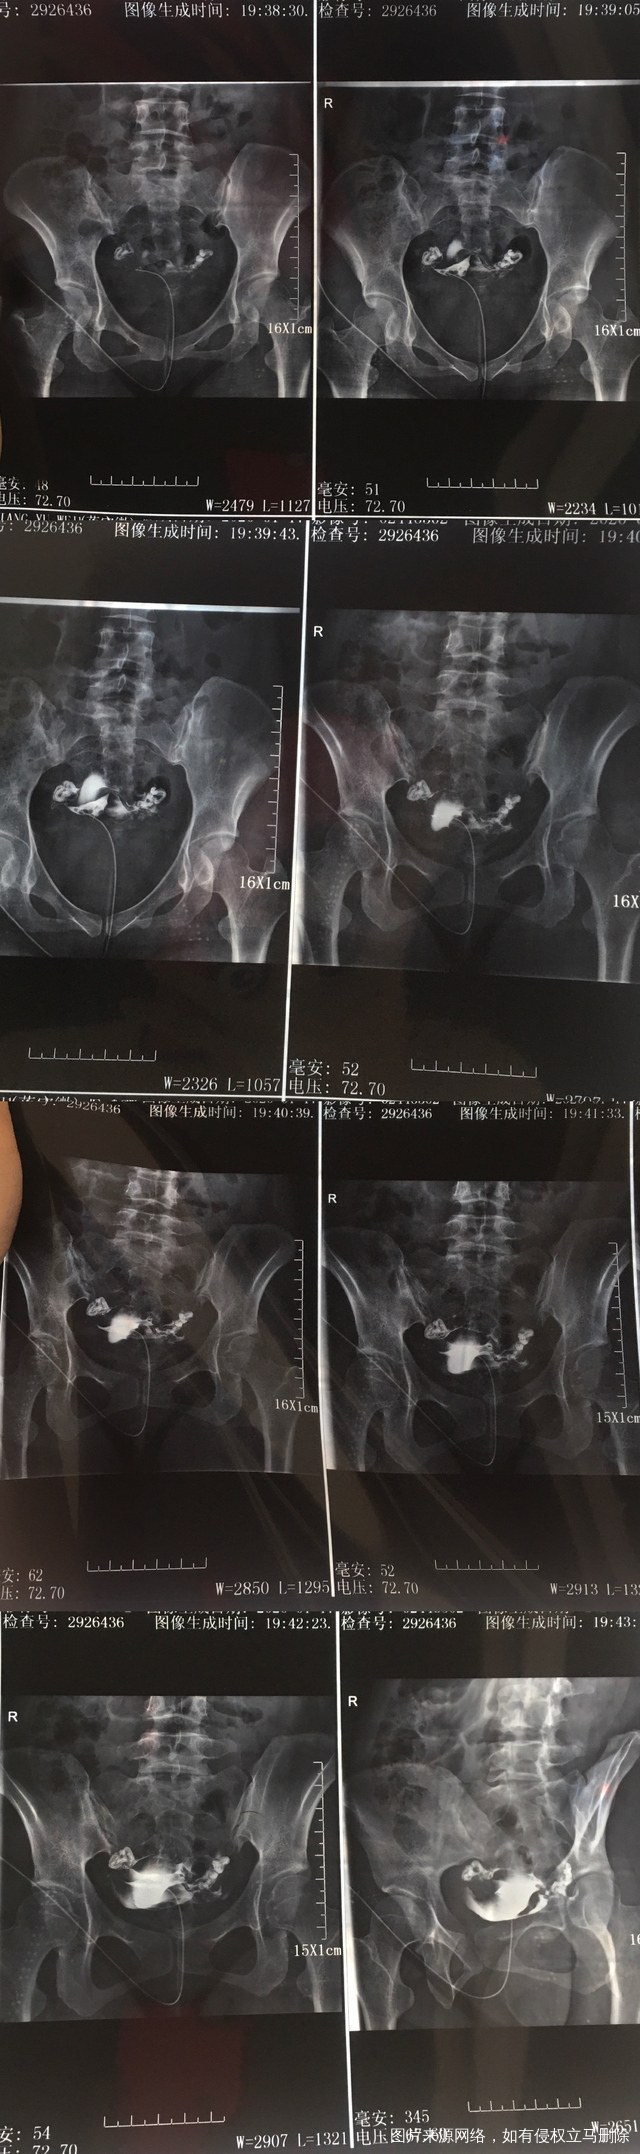

希望可以帮我看见输卵管造影片